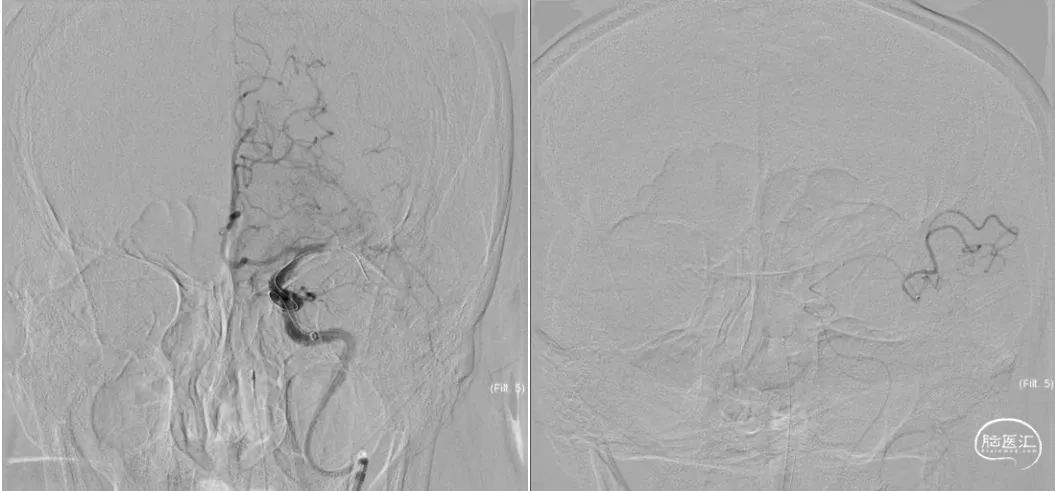

入院DSA:III型主动脉弓,后循环代偿不足,见图3,前交通动脉开放,左侧大脑前动脉通过软脑膜枝向左侧大脑中动脉供血区部分代偿,左侧颈内动脉起始部闭塞,左侧颈外动脉通过眼动脉向颈内动脉部分代偿,左侧大脑中动脉血栓形成,TICI分级0级,见图4。

图3.DSA造影:主动脉弓及左侧左侧椎动脉造影

图4.DSA造影:右侧颈内动脉正位及左侧颈内动脉侧位造影